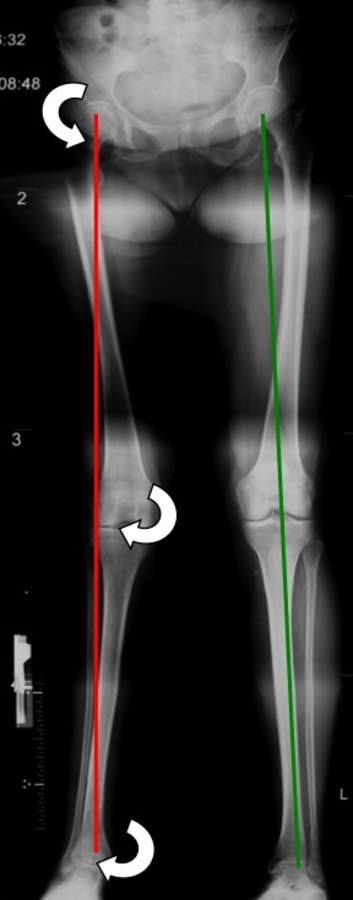

Figure 2

Long leg film with right side genu valgum and advanced ankle arthritis. The white arrows indicate the abduction moments on each joint resulting from the deviated mechanical axis.

The mechanical axis or alignment of the lower extremity is defined as a line drawn from the centre of the femoral head to the centre of the talus. The hip-knee-ankle alignment is best assessed with long leg films (fig. 2). This line passes close to the centre of the tibial head between the eminentia tibiae, approximately 1° in varus (neutral alignment 0–2°) [48]. Therefore, the medial compartment of the knee sustains 60–70% of the load [46, 48]. This physiologically imbalanced dispensation may be a predisposing factor to medially accentuated tibio-femoral OA. A varus-aligned knee is described as “bow-legged” and a valgus-aligned knee is described as “knocked-knee". This valgus or varus alignment have been described to influence the load distribution across the articular joint surface [49]. This asymmetry reduces the area of load bearing and amplifies the resultant load to the remaining joint surface. The deviation of the mechanical axis does strongly correlate with radiographic joint space narrowing, subchondral cyst formation, bone sclerosis, and functional decline in OA [49].